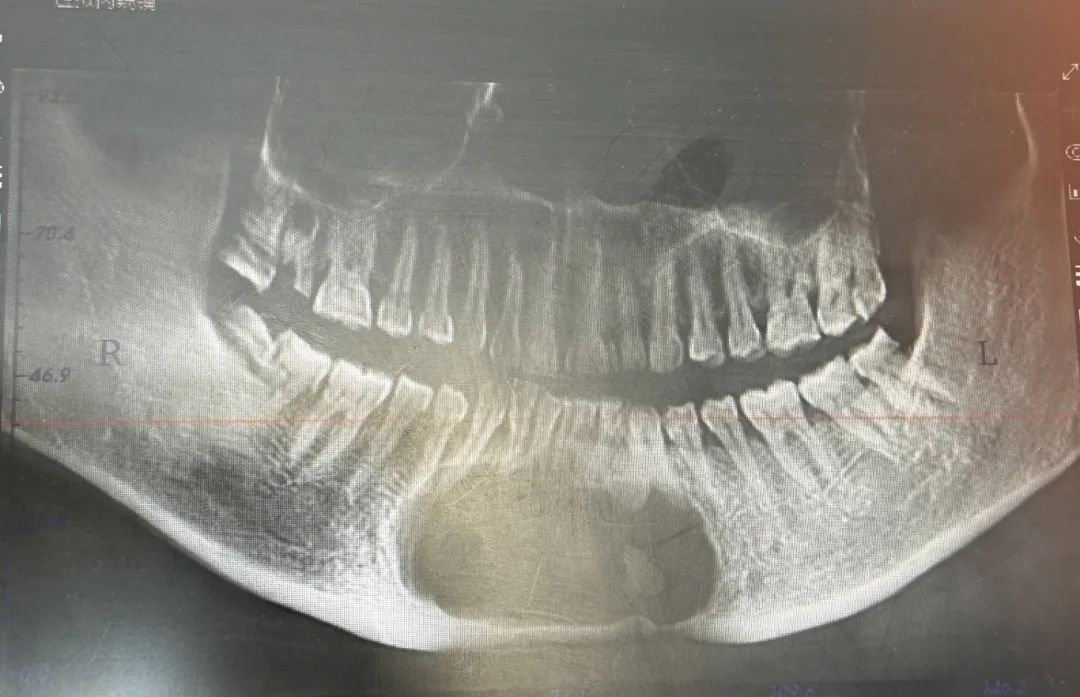

一直到王冠拿到檢查片子后,他終于明白當(dāng)?shù)蒯t(yī)生為什么不愿意為王阿姨手術(shù)——位于下頜骨中端(約為下巴處)的囊腫巨大,約有鵝蛋大小,且因時間過久導(dǎo)致下頜骨中端下緣已被吸收成線狀,“說白了,您的部分下頜骨薄的像紙一樣,哪怕您稍微用力咬合都有骨折的可能。切除囊腫的過程中,下頜骨很容易斷掉,那就麻煩了?!?/span>

囊腫巨大,累及7顆牙位,可以說整個下巴被囊腫占滿,骨頭一直在被吸收,手術(shù)迫在眉睫但難度很高??粗醢⒁虩o助的眼神,張雪林和王冠決定搏一把。

長約7公分的囊腫,下頜骨頰側(cè)骨質(zhì)呈乒乓球感,鈍性完整摘除囊壁后,置入重建板固定下頜骨,拔除病灶牙,修整牙槽骨……歷時2個半小時,憑借術(shù)者精湛的技藝、豐富的臨機(jī)處置能力、默契的配合,下頜骨腫物摘除術(shù)+下頜骨缺損鈦板重建術(shù)順利完成。